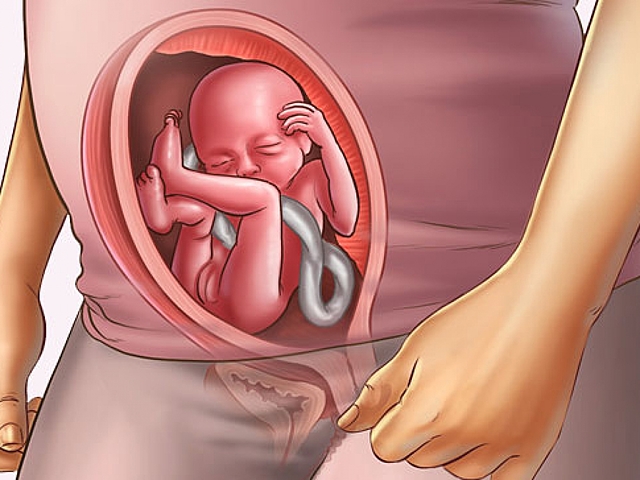

• Semana 20

Semana 20

El bebé se chupa el dedo, y sus movimientos son más rápidos, el bebé mide 25 centímetros desde la cabeza hasta los dedos de los pies, ahora traga más liquido de la bolsa en la que se encuentra y esto hace que su sistema digestivo comience a trabajar.